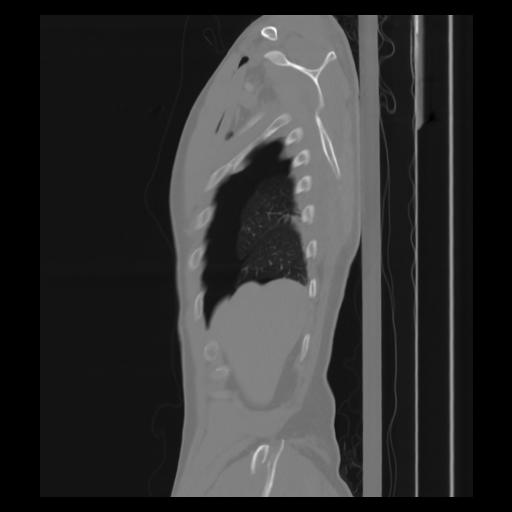

30 CUERPO,CE,Sagittal,3.000,CUERPO,Sagittal,